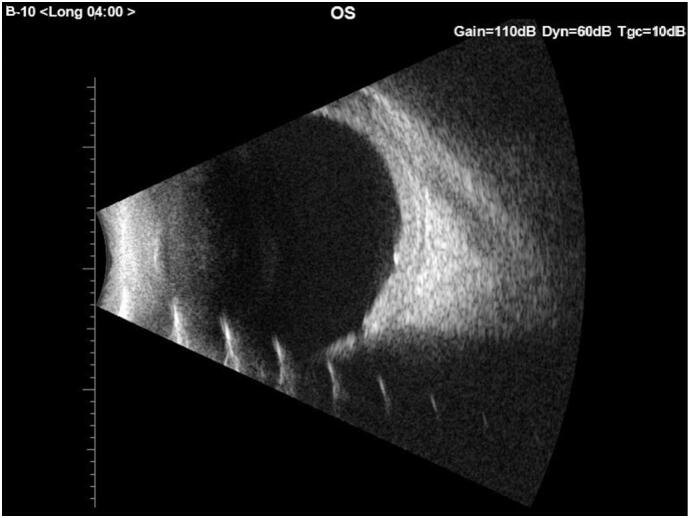

Fig. 3.

B scan ultrasonography of the left eye showing a foveal coloboma and no other significant findings.

EUA revealed an IOP of 14 mm Hg in the right eye and 20 mm Hg in the left eye. Corneal diameter as 12 mm in the right eye and 13 mm in the left eye. The axial length was 20.13 mm in the right eye and 21.75 mm in the left eye. The ocular examination in the left eye indicated a clear enlarged cornea with a quiet eye (Fig. 1). The anterior chamber was deep and quiet with a clear lens in the left eye. In the left eye, dilated fundus exam showed foveal coloboma which to our knowledge has not been reported before in cases of SWS. The fundus exam also showed diffuse choroidal hemangioma nasal to the disc. Retcam (Natus Medical, Inc., Pleasanton, CA USA) was used to obtain bilateral fundus photos for documentation and follow up (Fig. 2A,B) The discs had 0.5 vertical cup-to-disc ratios (Fig. 2A,B). The patient's cycloplegic refraction was +2.5 D in the right eye and −5.5 D in the left eye. B-scan was performed on the left eye and that confirmed the foveal coloboma (Fig. 3). As an option to reduce her IOP we elected to preform micropulse cyclophotocoagulation (MPCPC) in the left eye. We proceeded with MPCPC only in the inferior hemisphere with power of 2500 mw and duration of 80 s. The superior hemisphere was avoided in case the patient required filtration surgery in the future. To address her amblyopic left eye and fixation preference, patient was given glasses and patching on her latest follow up visit with pediatrics.